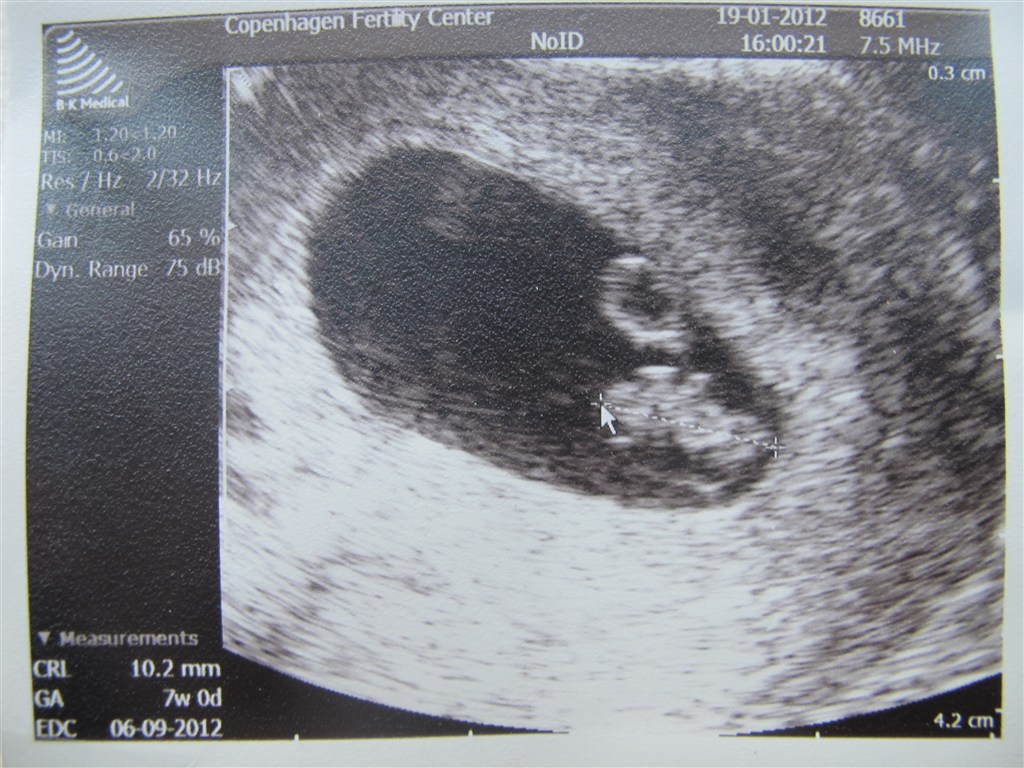

Er SÅ glad.....i går var min mand og jeg på CFC og jeg blev scannet. Vi så den fineste lille minion med hjerteblink!!! Helt fantastisk!!!!

Rettelse: jeg studerede lige billedet lidt nærmere og så- 7+0.